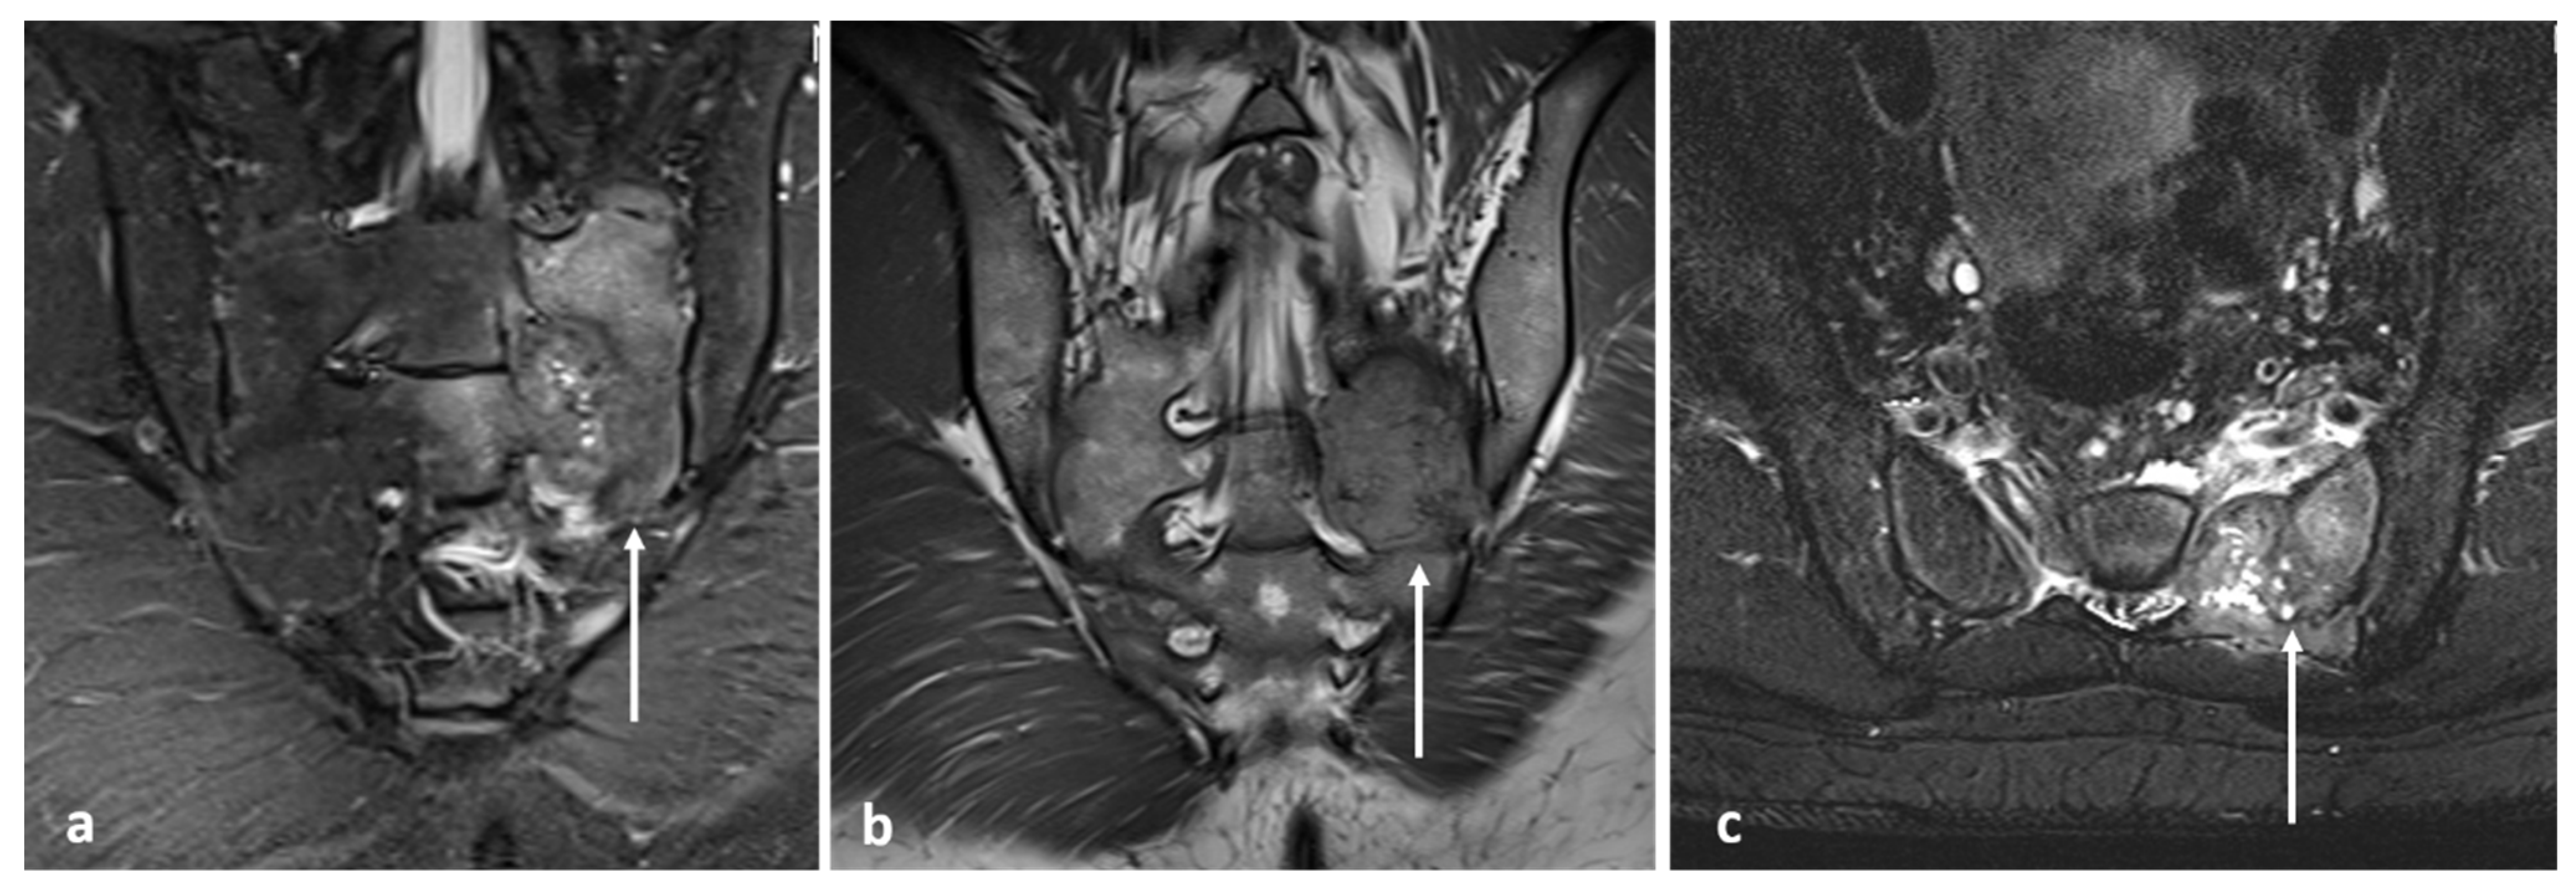

3.9. Aneurysmal Bone Cyst

| Aneurysmal bone cyst | Expansile lytic lesion with internal bone septations. | Fluid—fluid levels within the cysts, high T1 signal within layering fluid content due to haemorrhage. |